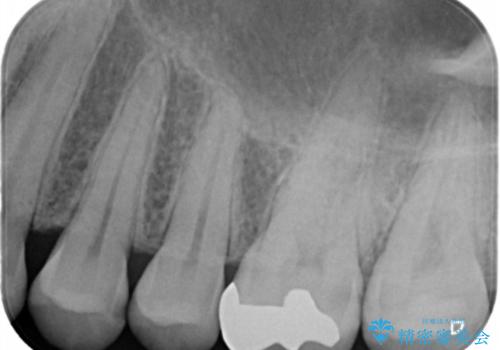

- 銀歯のやり替えと虫歯の治療をご希望で来院された患者様です。

一番奥の歯は外から見えにくい部分であるためゴールドインレーで修復します。

その他はセラミックインレーで修復します。

- 左上46:セラミックインレー/77,000円×2 左上7:ゴールドインレー/77,000円×1費用は治療当時の料金となります

噛みしめの強い方や、外から見えないような部分では、割れる心配のないゴールドインレーをおすすめします。